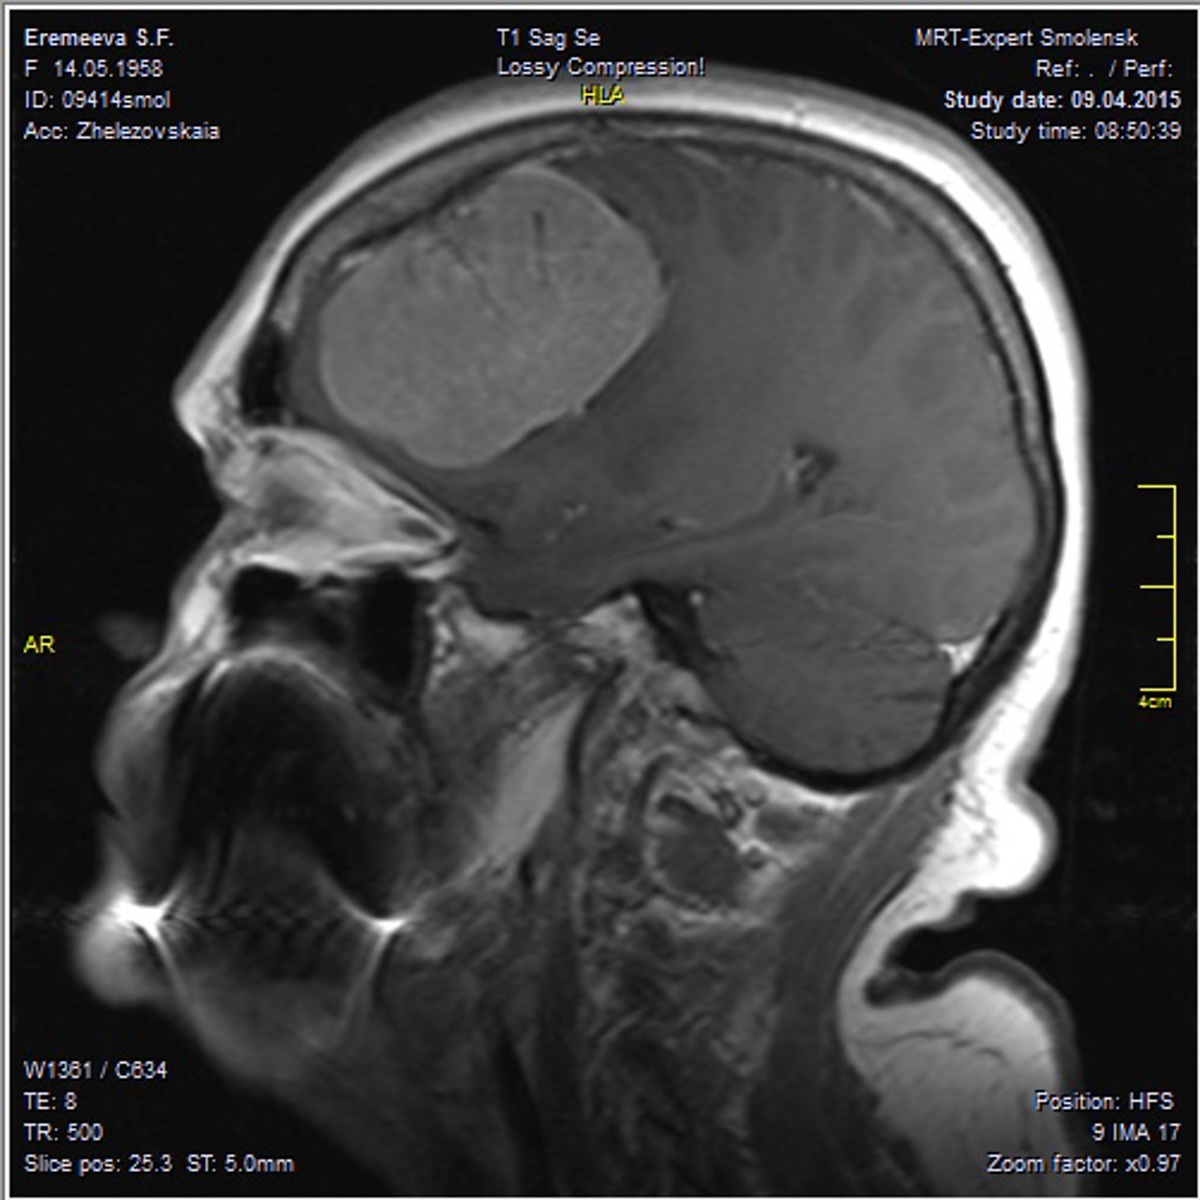

- Комплексная диагностика. Проводятся высокоточные исследования: магнитно-резонансная томография (МРТ) с контрастированием, компьютерная томография (КТ), ангиография сосудов головного мозга. Эти методы позволяют хирургу увидеть точное расположение, размер и структуру образования, а также его взаимоотношение с сосудами и функциональными зонами мозга.

- Долгосрочная реабилитация. После выписки начинается самый важный этап. Он может включать занятия с физиотерапевтом для восстановления двигательных функций, с логопедом для коррекции речевых нарушений и с нейропсихологом для улучшения памяти, внимания и мышления. Важно строго следовать рекомендациям врача, принимать назначенные препараты и регулярно проходить контрольные обследования (МРТ, КТ).

- Долгосрочное наблюдение. После операции необходимо регулярно проходить контрольные осмотры у нейрохирурга и делать МРТ или КТ головного мозга, чтобы отслеживать процесс восстановления и вовремя выявлять возможные рецидивы заболевания.